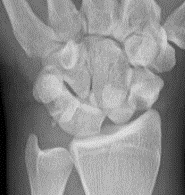

AP X-ray

Disruption of Gilula's 3 smooth carpal arcs / triangular lunate

Normal versus disruputed Gilula's carpal arcs

Piece of pie / triangular appearance of lunate

CT

Trans-scaphoid perilunate dislocation

Perilunate dislocation